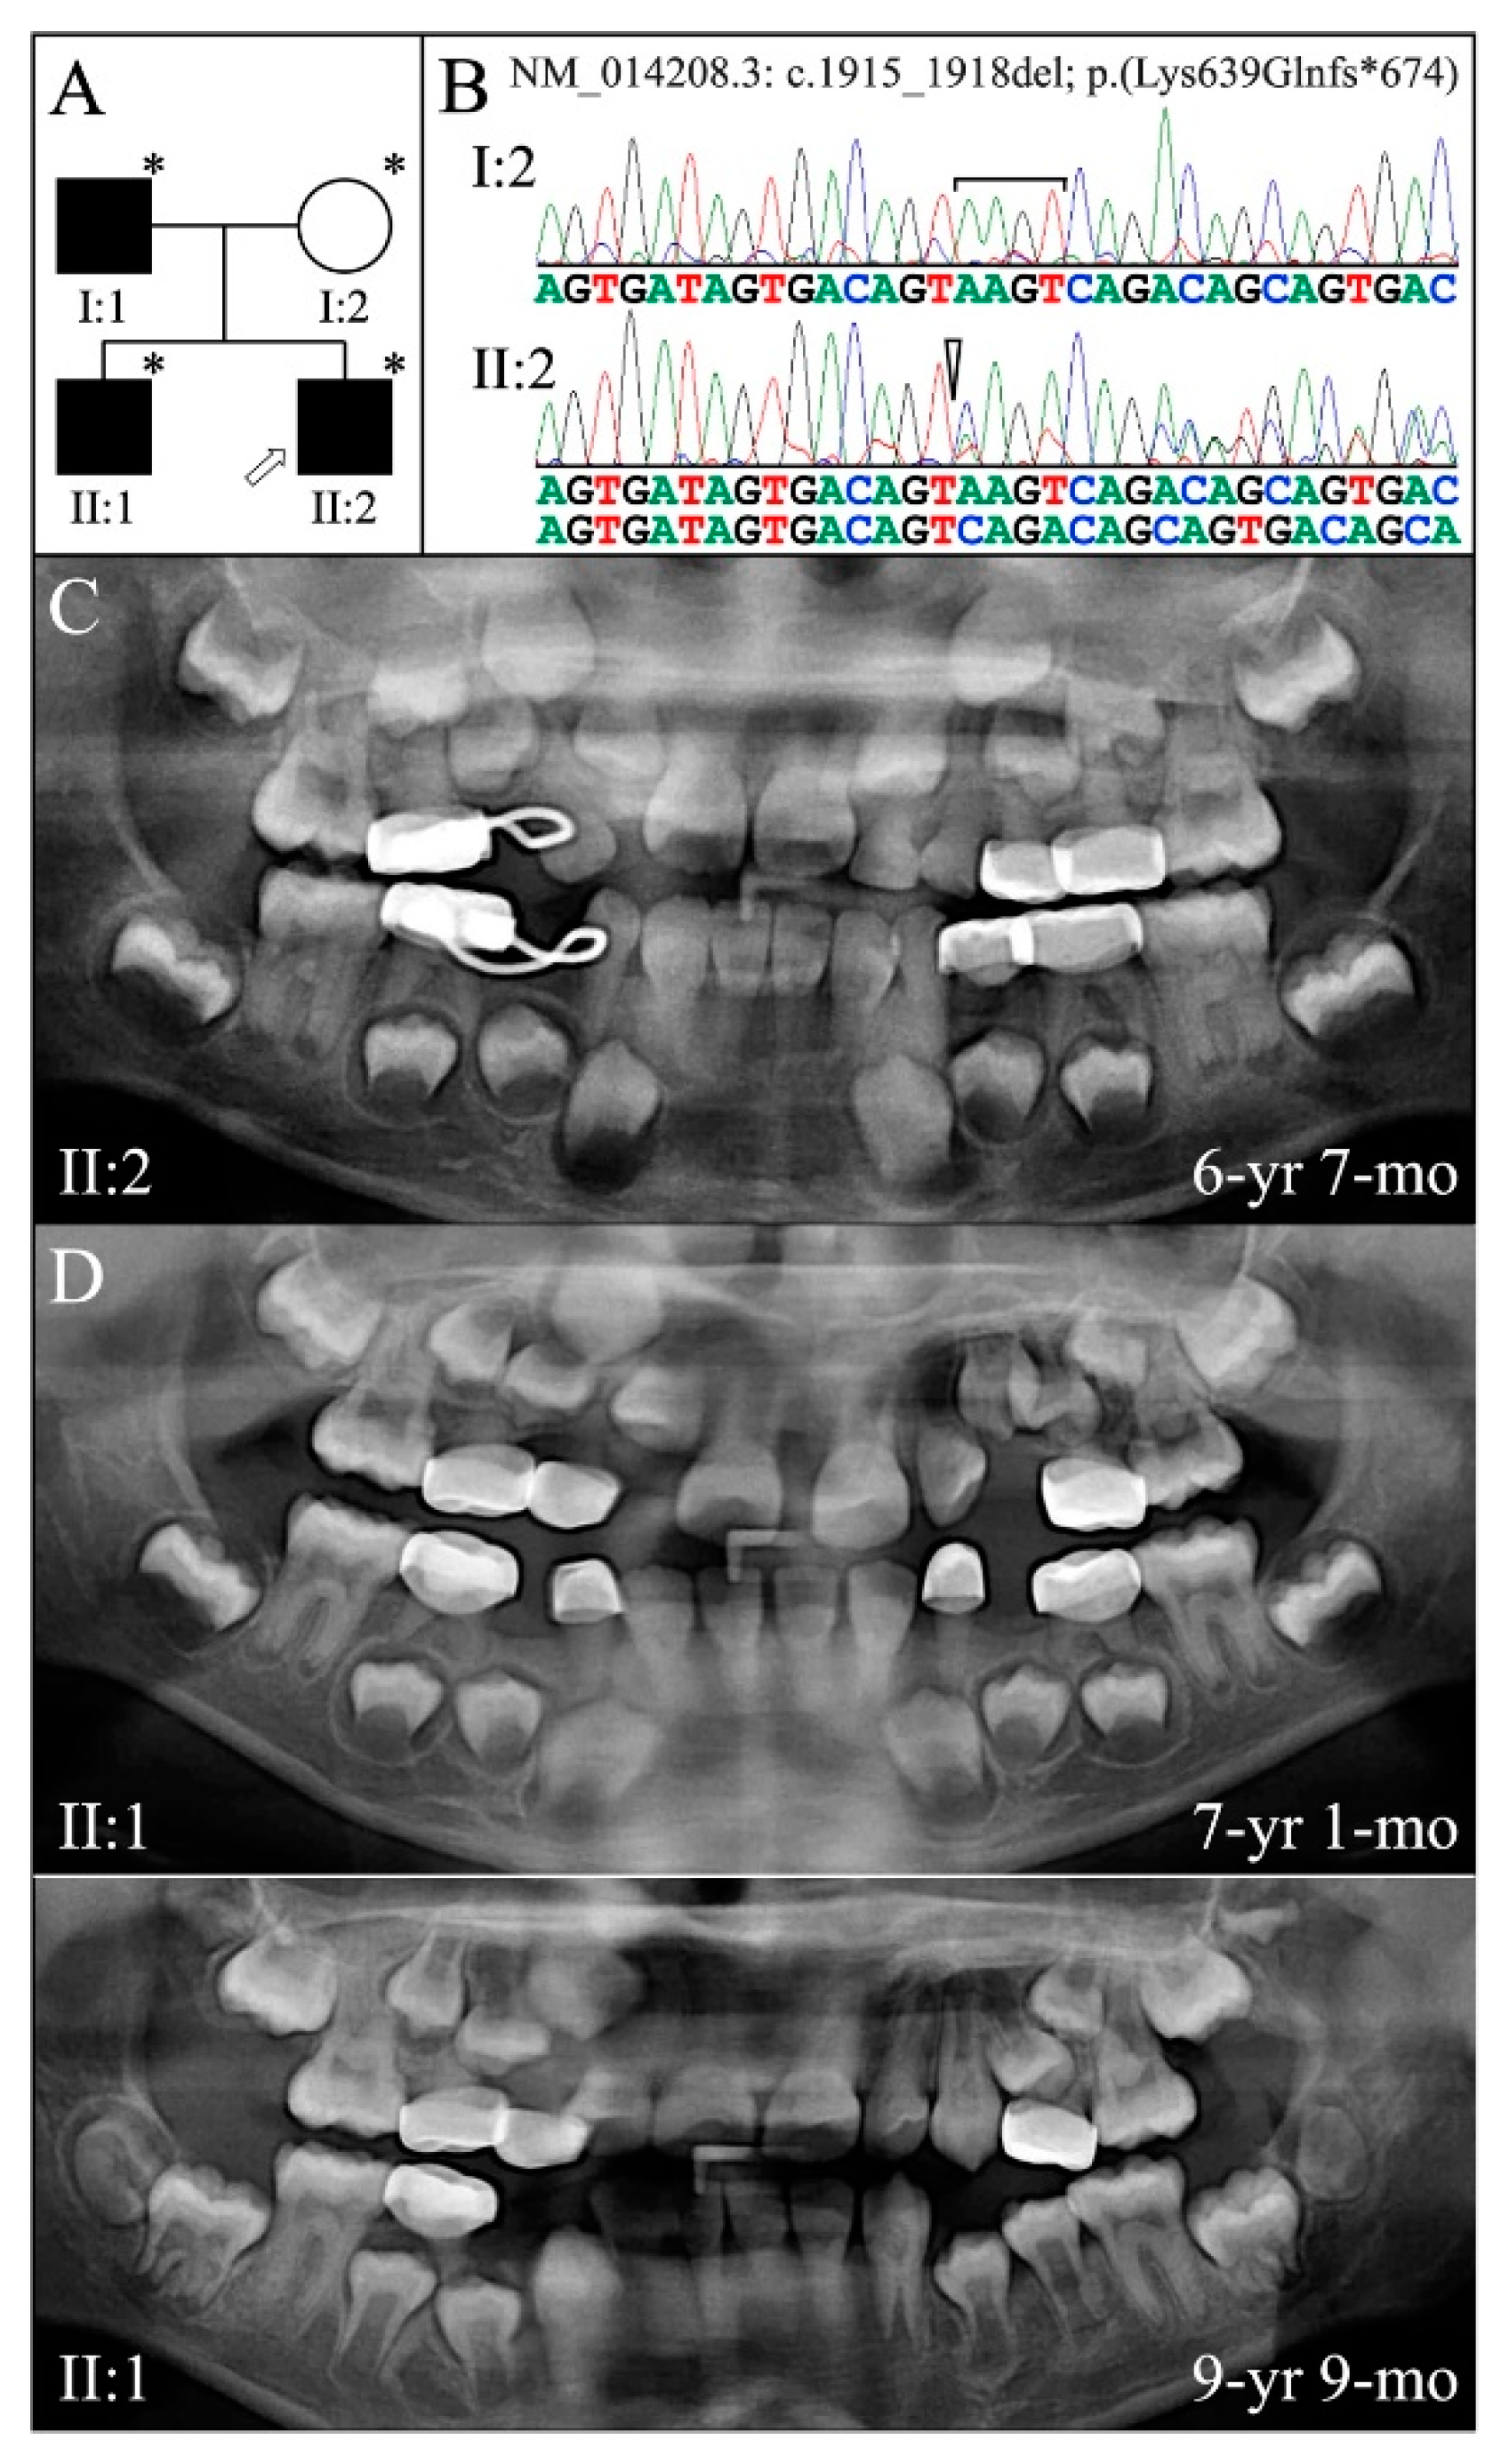

3.3. Eight Families with 3′ DSPP Mutations Causing DD-II or DGI-II

| 5 | g.11049_11052delAAGT | c.1915_1918delAAGT | p.(Lys639Glnfs*674) | Family 5 [82] |

| 5 | Illumina HiSeq 2500 (WES) | NG_011595.1:g.11049_11052delAAGT; NM_014208.3:c.1915_1918delAAGT; NP_055023.2: p.(Lys639Glnfs*674) | −1 Frameshift | I:1, affected father: 233.91× I:2, unaffected mother: 165.19× II:2, affected 2nd child: 178.45× |